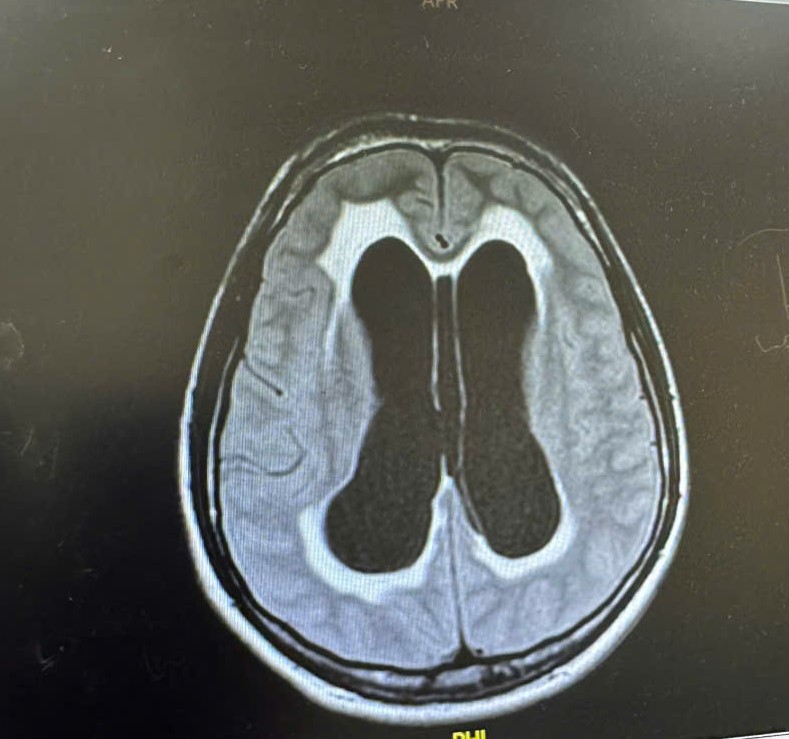

Hình ảnh CT sọ não cho thấy, não thất giãn rộng bất thường. Ảnh: BV

Kết quả chụp CT cho thấy, não thất của bệnh nhân giãn rộng bất thường, đối mặt với nguy cơ hôn mê sâu, ngưng thở và tử vong. Ngay lập tức, các bác sĩ đã tiến hành đặt dẫn lưu não thất ổ bụng (VP Shunt) để giảm áp lực nội sọ.